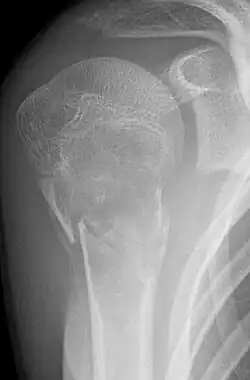

Eine Knochenzyste ist eine gutartige tumorähnliche Knochenläsion, welche einen flüssigkeitsgefüllten und z. T. zellgefüllten Hohlraum im Knochen darstellt. Radiologisch erkennt man hier im Röntgenbild eine ein- oder mehrkammerige Aufhellung. Die Zysten im jugendlichen Knochen werden meist als Zufallsbefund beim Röntgen nach Unfallverletzung oder als Ursache von sogenannten pathologischen Frakturen (Frakturen bei verringerter Knochenfestigkeit) entdeckt.

- Einfache (juvenile) Knochenzyste: Gutartige, primär einkammerige, flüssigkeitsgefüllte Höhle, meist im metaphysären Markraum. Wird meist erst durch Spontanfraktur auffällig. Klassisches Röntgenzeichen ist das Fallen-Fragment-Sign.

- Aneurysmatische Knochenzyste (AKZ): Gutartige, mehrkammerige Knochenläsion. Klassischer Befund in der MRT ist die „Spiegelbildung“ des Zysteninhaltes mit unterschiedlichen Signalintensitäten.